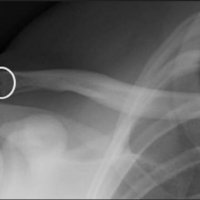

AC joint separation, often called a shoulder separation, is a dislocation of the clavicle from the acromion, with disruption of the acromioclavicular ligaments and/or coracoclavicular (CC) ligaments.

This injury is usually caused by a blow to the shoulder, or a fall in which the individual lands directly on the shoulder or an outstretched arm.

Treatment is immobilzation or surgical reconstruction depending on the degree of separation and ligament injury.

Rockwood Classification:

X-Ray Findings